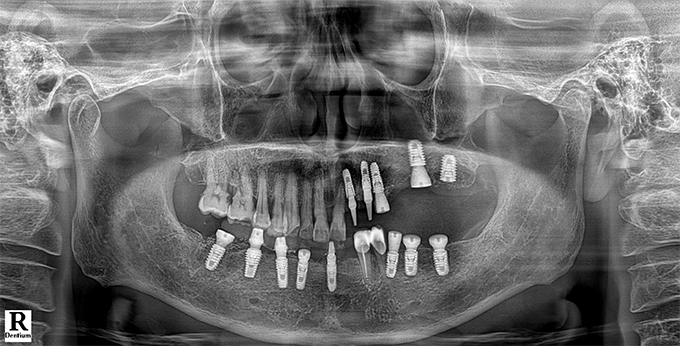

Before & After

임플란트 전후사진

before

2022.11.22

After

2022.12.09

※ 상기 치료전후 사진은 환자의 동의 하에 게재되는 것이며 동일한 촬영각도로 촬영 하였고 치료 기간을 명시하였습니다.

이러한 치료의 결과는 이 환자분에게만 해당되는 것이며 환자의 상태에 따라 똑같은 결과를 얻지 못할 수도 있습니다.

환자분의 상태에 따라 치료 기간, 효과 및 부작용은 상이할 수 있습니다.

치료전후 사진 게재는 의료법 제 23조, 제56조에 의거하여 게재합니다.